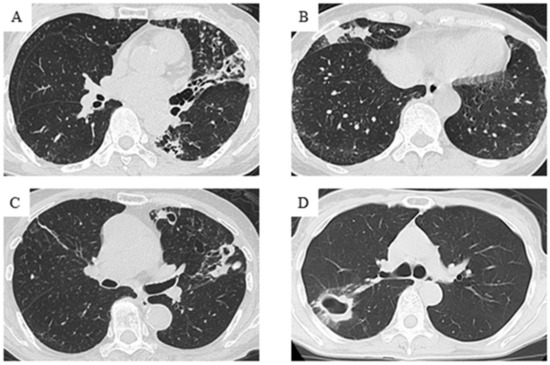

2.4. Radiological Evaluation

| Chest CT findings | ||||

| Non-cavitary NB | 102 (70.8) | 40 (64.5) | 62 (75.6) | 0.15 |

| Cavitary NB | 33 (22.9) | 18 (29.0) | 15 (18.3) | 0.13 |

| FC | 6 (4.2) | 4 (6.5) | 2 (2.4) | 0.23 |

| Unclassified | 3 (2.1) | 0 (0.0) | 3 (3.7) | 0.13 |

| Cavitary NB+FC | 39 (27.1) | 22 (35.5) | 17 (20.7) | <0.05 |